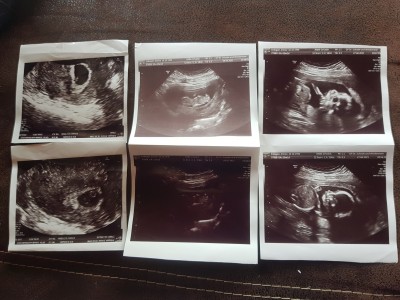

Sizce by teoriye göre bebeğim kızmı erkekmi

Gebelik haftası 18

Kapatılma nedeni: Cinsiyet tahminlerini sol üst köşeden konu dışı sohbetten sorabilirsiniz

Bence kıza benziyor